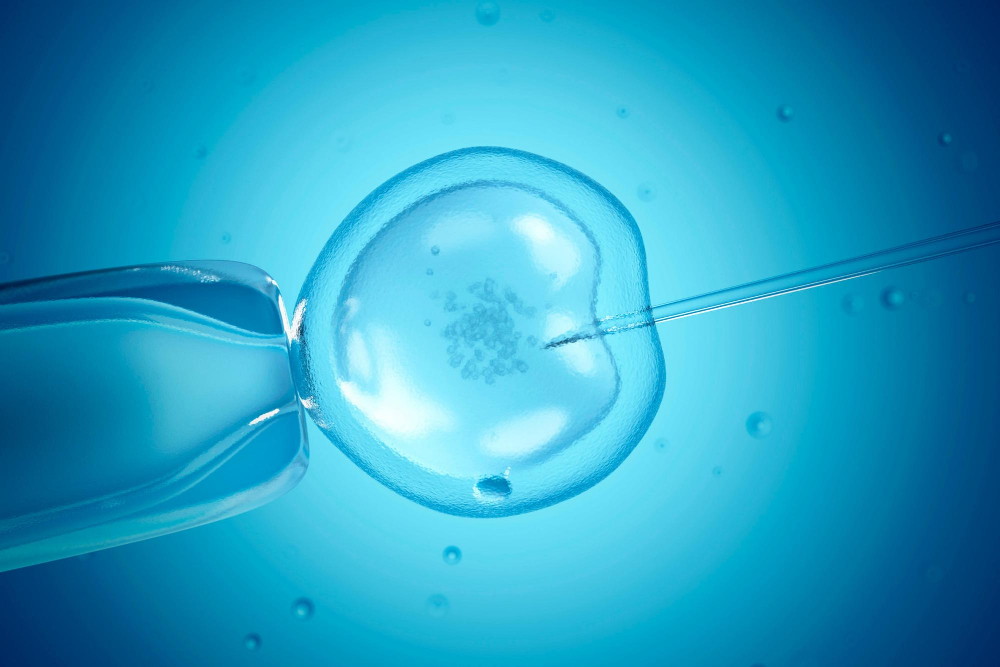

Maroc-Fertilité est un centre spécialisé dans la prise en charge de l’infertilité et de la procréation médicalement assistée (PMA), situé au cœur de Casablanca.

Notre mission est simple : offrir aux couples du Maroc, d’Afrique et de la diaspora un accès aux techniques les plus avancées de fertilité, dans un cadre humain, sécurisé et transparent. Nous croyons que chaque parcours de fertilité est unique. C’est pourquoi nous proposons une approche globale, personnalisée et fondée sur les standards internationaux en reproduction médicale.

Notre centre utilise des techniques de PMA et de diagnostic reconnues pour leur fiabilité :

- FIV et ICSI,

- Insémination intra-utérine,

Notre laboratoire suit des standards stricts afin de garantir une qualité maximale à chaque étape du processus.